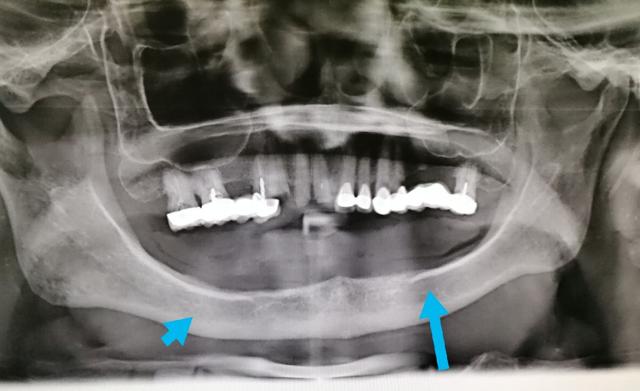

2002年,我还在医院上班的时候接待一位35岁左右的男性顾客,他在口腔里面仅有十几颗摇摇晃晃的牙齿,拍完片以后,我当天就把他所有的牙齿一次性拔光,有些牙齿拔出来的时候甚至都没有出血……

通过对他从事的职业了解到(这里隐去他所从事的工作),他在工作当中经常会接触到一些相关的化学物品,而他们的防护工作做得很不到位……

无独有偶,我的另一位顾客朋友在矿山工作,在40岁的时候,全口牙快掉光了,只剩下下面几个门牙在那里摇摇欲坠,大家知道在选矿的时候也会接触到一些有毒的化学物品……

尚不能肯定地判断他牙齿掉光的原因就跟这些化学物品有关,但是我真的希望从事类似工作的一些朋友,你们要认真的做好个人的防护工作